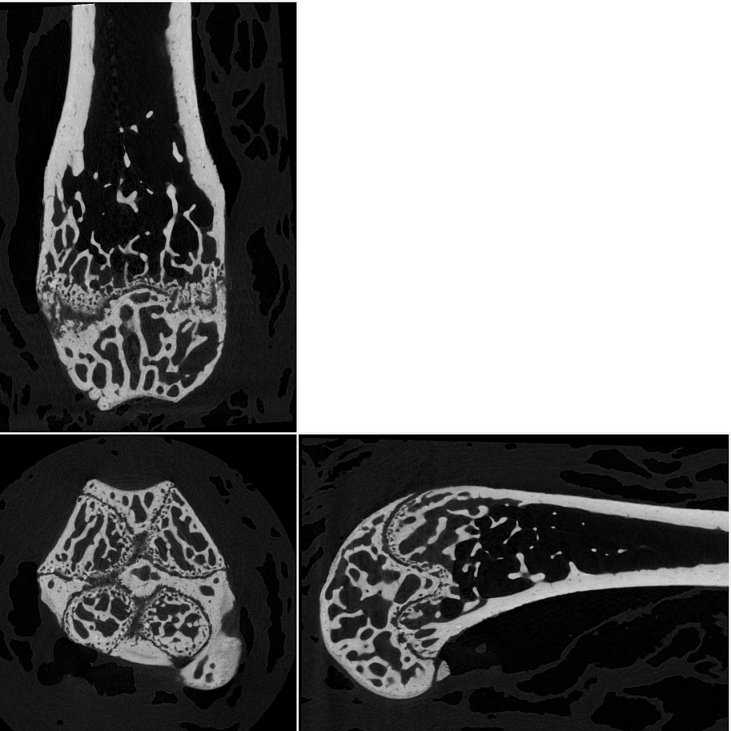

8. Orthogonal slices through a mouse femur, scanned at 2.8 umvoxel size.